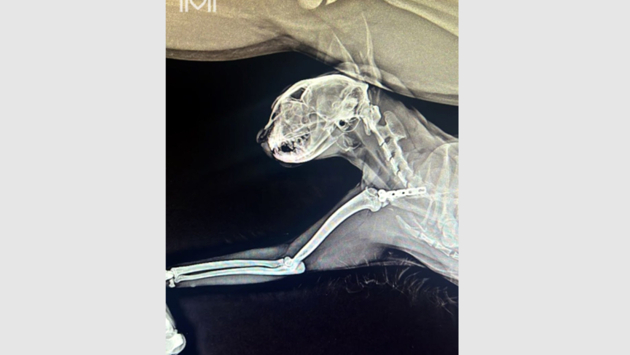

Московские ветеринары спасли кошку по кличке Нора, которая упала с восьмого этажа. Ей провели операцию по остеосинтезу с использованием металлических пластин после тяжелого перелома, сообщает ГБУ «Мосветобъединение» в своем Telegram-канале.

Как уточнили в учреждении, кошку после падения с восьмого этажа отвезли в одну из ветклиник, где ей оказали первую помощь и стабилизировали состояние, однако Норе была необходима операция по остеосинтезу из-за сломанной лопатки. Впоследствии в Мосветстанции кошке-метису провели стабилизацию линии перелома за счет установки Т-образной пластины.

«Остеосинтез с использованием металлических пластин позволяет сократить сроки реабилитации животного, дает возможность ранних физических нагрузок на травмированную конечность», -- рассказал ведущий ветеринарный врач, хирург-ортопед Мосветстанции Александр Степанов.